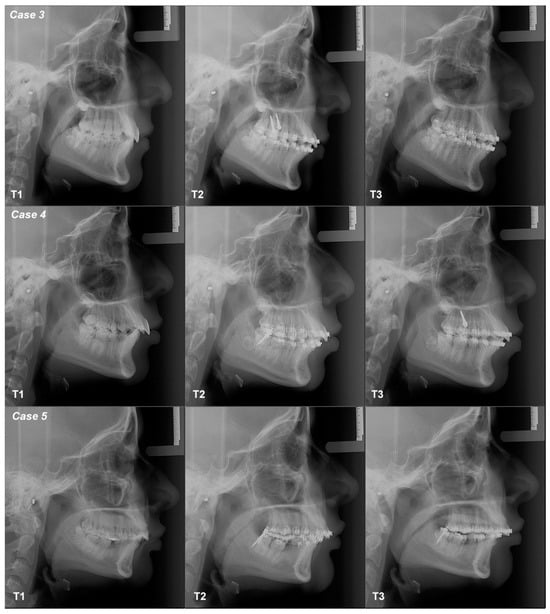

3.2.3. Case 3

3.2.4. Case 4

3.2.5. Case 5